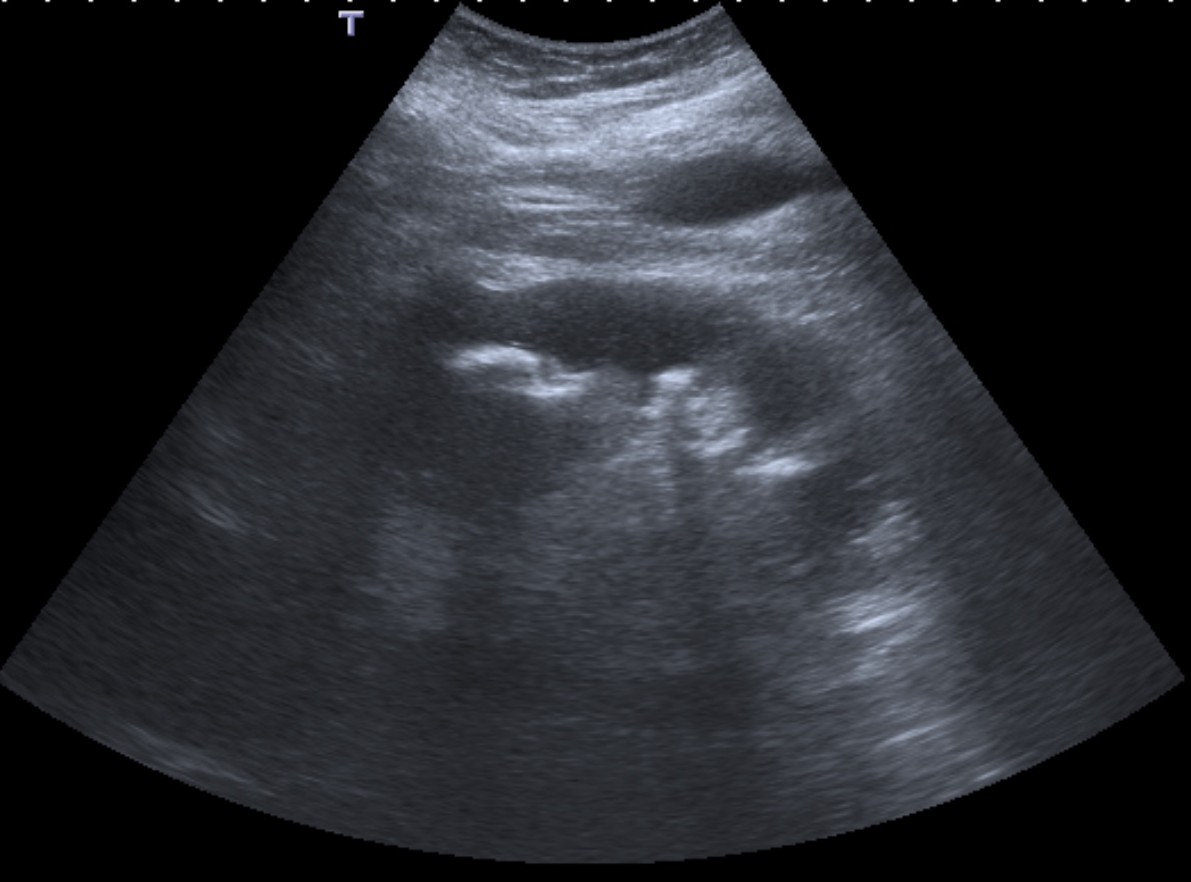

- En placa simple podía verse un masa que renal con o sin borramiento de la línea del psoas. En ecografía, cálculos y aumento del tamaño renal en la forma difusa con múltiples áreas anecoicas correspondientes a las colecciones purulentas.

- Los hallazgos en TC pueden ser:

- Uni o bilateralidad de la lesión.

- Afección difusa o localizado.

- Litiasis de tipo coraliforme, calcificaciones intraparenquimatosas.

- Aumento difuso del tamaño renal.

- Áreas hipodensas o hipoecogénicas dentro de la lesión renal debidas a cálices dilatados, abscesos o áreas de necrosis parenquimatosa.

- Pobre o nula eliminación del medio de contraste en el riñón afectado.

- Compromiso inflamatorio que excede los límites del riñón y genera colecciones periféricas o extensión hacia vísceras vecinas.